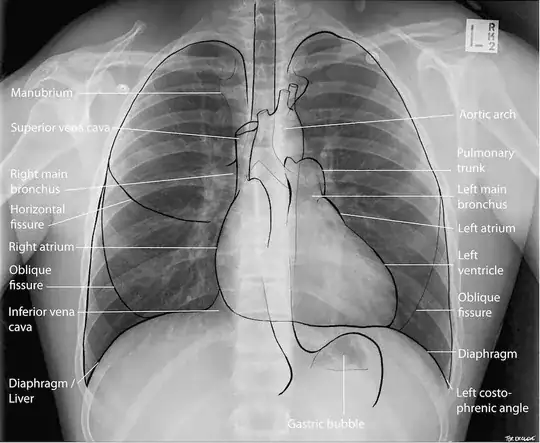

Below is an X-ray image of the chest cavity. You can see the big letter "L" and all the "left" terms on the right side of the image, because this is a view from the front, so they are all point to the left parts of the body. The confusion could occur when someone points to the image and just says "here on the left," without saying "side of the body " or "image." Anyway , when a doctor says something is on the left side, it should be always on your left.

(Source: Lifeinthefastline, CC licence)